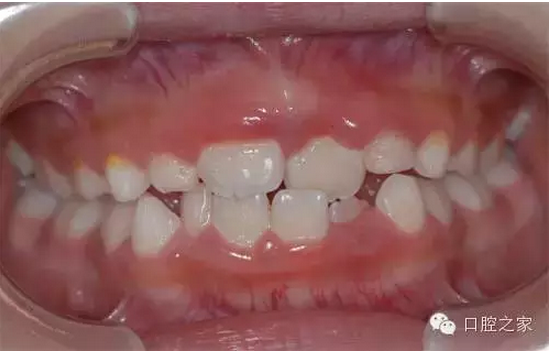

什么是前牙反合?

上下牙弓近遠(yuǎn)中關(guān)系異??杀憩F(xiàn)為下頜前突,近中錯(cuò)合及前牙反合。多由于不良哺乳姿勢(shì),乳前牙滯留或早失,上恒切牙先天性缺失,不良習(xí)慣、乳尖牙磨耗不足,全身性疾病以及遺傳性下頜前突所致。因程度不同可表現(xiàn)為前牙反合,磨牙為中性合,嚴(yán)重病例則前牙反合、后牙近中合及下頜前突同時(shí)存在。

臨床表現(xiàn)

前牙反,顏面可表現(xiàn)為下頜前突,上頜發(fā)育不足的凹形側(cè)面形。